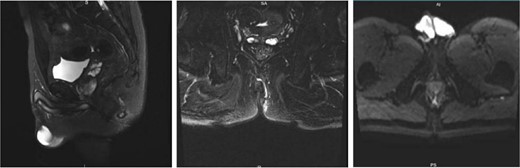

A 43-year-old male patient was admitted in July 2022 due to an anal fistula. The patient had a 15-year history of recurrent perianal abscesses with prior surgical intervention in 2007, 2011, and 2012. However, following each surgery, the wounds failed to heal completely, resulting in persistent drainage of purulent fluid through the external orifices and intermittent recurrence of perianal abscesses. Two weeks before admission, the patient reported a significant increase in perianal pain. Notably, the patient had no history of inflammatory bowel disease, but had been diagnosed with HIV infection for 10 years. Physical examination revealed two external fistulous orifices located at the 3-o’clock and 9-o’clock positions, ~3 cm from the anal verge. Rectoscopy confirmed that the internal opening was situated within the anal crypt at the 6-o’clock position, and laboratory tests conducted upon admission did not reveal any abnormalities. Colonoscopy was performed and no underlying intestinal pathology was identified. Perianal magnetic resonance imaging revealed an intersphincteric fistula (Fig. 1).The patient underwent surgical intervention and the resected fistula tract was subjected to histopathological examination, which yielded a diagnosis of squamous cell carcinoma (Fig. 2). Consequently, the patient was not offered further surgical treatment at our institution but was referred to a specialized center for radiotherapy. During a 2-year follow-up after radiotherapy, the patient reported complete remission of the disease with no evidence of locally recurrent cancer cells. However, the surgical wound remained partially healed.

Preoperative perianal magnetic resonance imaging (MRI) examination.